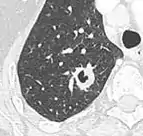

| CT scan of the lung showing bullae in the lower lung lobes of a subject with type alpha-1-antitrypsin deficiency. There is also increased lung density in areas with compression of lung tissue by the bullae. | |

- A cavity has a wall thickness of more than 4 mm.[2]